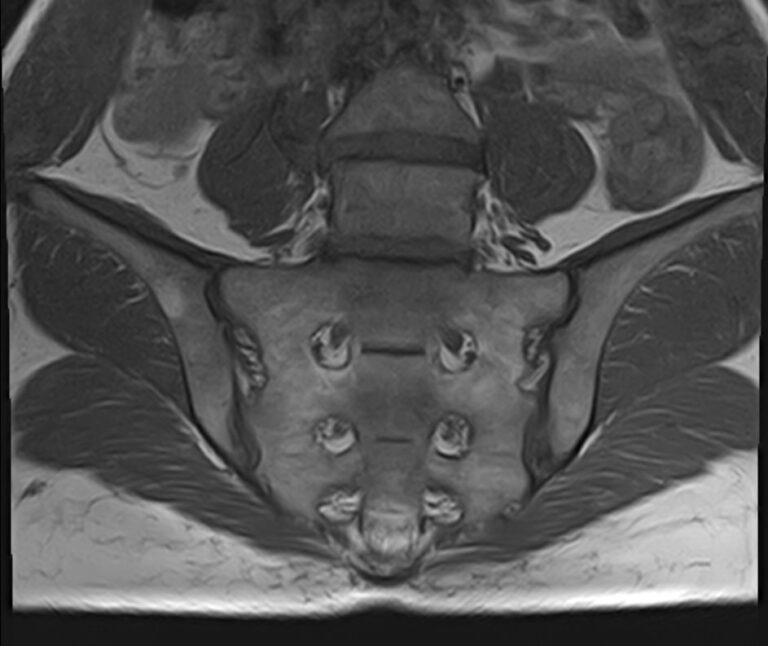

Крестцово-подвздошное сочленение – это крупный малоподвижный сустав, место соединения крестца и подвздошных костей, которое часто вовлекается в патологический процесс при травмах, дегенеративных поражениях, инфекциях и опухолевых заболеваниях.

С помощью МРТ можно диагностировать поражение крестцово-подвздошных сочленений на начальной стадии, когда другие методы не дают результатов. Такой патологией, в частности, является сакроилеит (воспаление крестцово-подвздошного сочленения), который часто становится причиной анкилоза (сращения) или нестабильности (патологической подвижности) сустава. Выявление сакроилеита на ранней стадии значительно улучшает прогноз в плане лечения и профилактики осложнений.

В клинике «Доступная медицина» диагностика патологии крестцово-подвздошных сочленений осуществляется на новейшем высокопольном томографе экспертного уровня TOSHIBA VANTAGE TITAN 1,5 Тесла. Аппарат проводит сканирование в различных плоскостях, делая срезы с шагом от 1 мм, затем с помощью компьютерных программ преобразует полученные данные в трехмерные изображения.

Что показывает МРТ крестцово-подвздошных сочленений

• Повреждения суставно-связочного аппарата в этой области;

• Дегенеративные и воспалительные процессы;

• Метастазы и опухолевые процессы. МРТ крестцово-подвздошных сочленений помогает выявлять новообразования на ранних стадиях, что не под силу многим другим методикам исследования. МРТ крестцово-подвздошного сочленения рекомендуют при наличии следующих жалоб пациента: